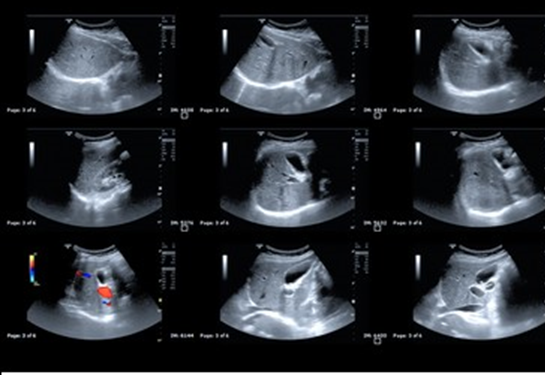

Wireless Dual Head Convex+Linear-ULC-210

Introducing ULC-210, the pinnacle of wireless ultrasound technology,

revolutionizing medical diagnostics with unparalleled convenience and precision.

Offering a comprehensive spectrum of ultrasound diagnoses, this cutting-edge

equipment seamlessly integrates with your smartphone or tablet. Through our

groundbreaking mobile app, you have full control over the ultrasound probe,

enabling effortless image collection from anywhere, at any time.

Experience the future of healthcare with ULC-210 by UltrasonoMed.

Our commitment to excellence ensures not only affordability but also

uncompromising quality in medical care. Empowering both clinical and

remote settings, our wireless ultrasound solution transcends boundaries,

delivering superior imaging capabilities to healthcare professionals worldwide.

Join us in shaping the landscape of modern medicine with innovation that knows

no bounds.

| CLINICAL APPLICATIONS | |

| Convex: | Abdomen, Cardiac, Gynecology, Obstetrics, Urology, Kidney, Lung |

| Linear: | Vascular, MSK, Breast, Pediatrics, Thyroid, Carotid, Small Organs, Nerve |